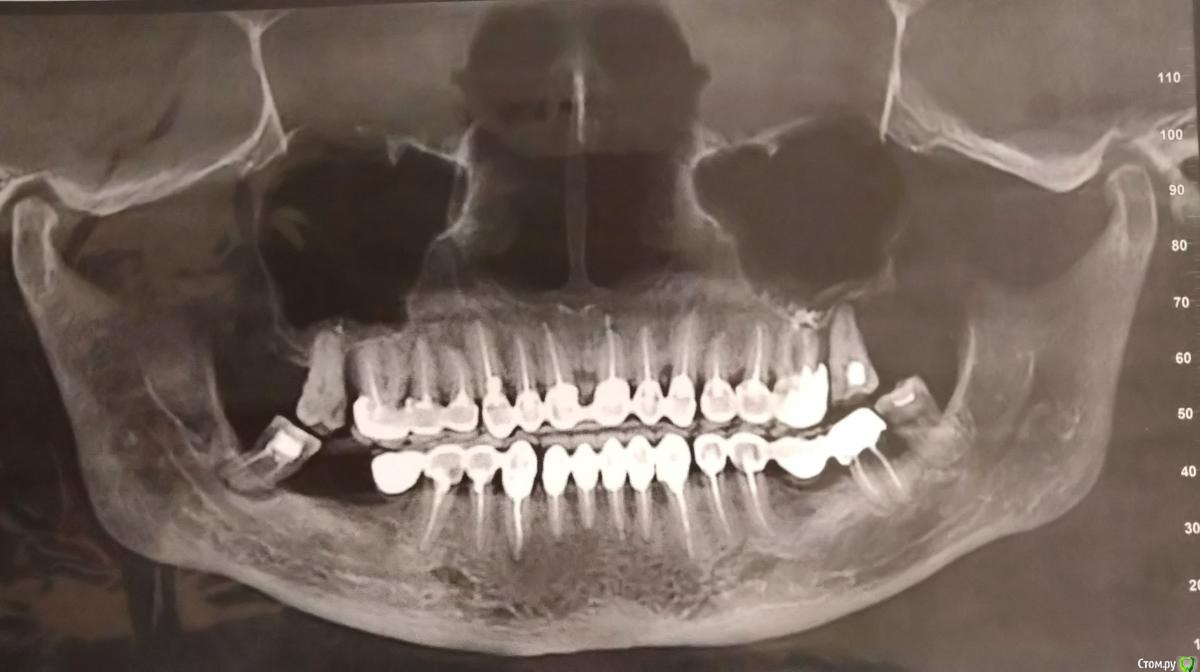

Svetlana Ivanova Опубликовано 21 февраля, 2020 Автор Поделиться Опубликовано 21 февраля, 2020 Свежий снимок, сделанный 15 минут назад. Ссылка на комментарий

krokomot Опубликовано 21 февраля, 2020 Поделиться Опубликовано 21 февраля, 2020 Здравствуйте, этот снимок ваш ортопед видел? На мой взгляд, соединение коронок близ лежащих зубов приводит к затруднению гигиены и как следствие усугубление состояния тканей пародонта. Состояние кости вокруг корней ваших зубов вполне удовлеторительно и они могут стоять не расшатываясь, при условии восстановление функции в боковом отделе, не очень понятно с дальними зубами. Консольный протез прилегает к зубам не очень хорошо. Я предпочитаю фиксировать на зубы пресованную керамику, так как граница прилегания к зубу может быть заполирована, а это важно для людей с склонностью к заболеваниям пародонта. 1 Ссылка на комментарий

krokomot Опубликовано 22 февраля, 2020 Поделиться Опубликовано 22 февраля, 2020 Что вам сказать?, похоже есть цемент в некоторых промежутках, там его быть не должно, коронки плохо прилегают к зубам, для более точного понимания о состоянии вещей делать нужно прицельные снимки на каждый зуб.Потребуется очный осмотр, сходите на консультацию к другому ортопеду, дискомфорта и вони, при адекватной гигиене не должно быть. 1 Ссылка на комментарий